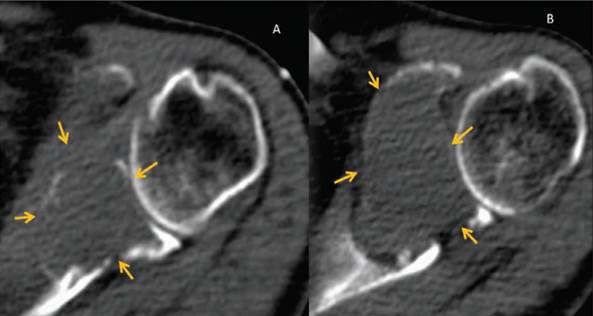

El paciente es tratado con 100 mg de talidomida por día, 40 mg de dexametasona semanal y se inició radioterapia, por lo que solicitaron tomografía en fase simple como protocolo (Figura 5), en el cual se observó la lesión expansiva a nivel de la escápula y múltiples lesiones líticas en arcos costales y cuerpos vertebrales dorsales compatibles con mieloma múltiple.